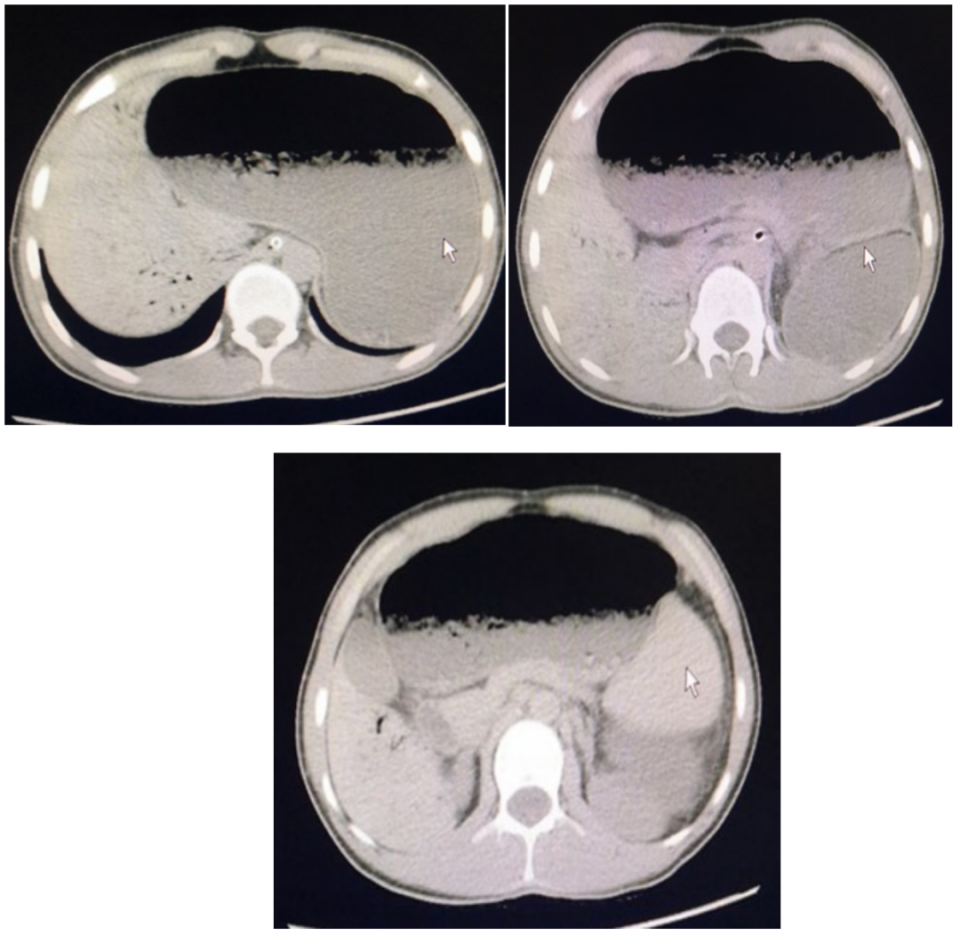

入院后给予禁食、抑制胃酸分泌、补液等对症支持诊疗,行上腹部CT检查,结果如下(图1):

图1

CT一看就和平常人的不一样,胃看着很奇怪。

结合患者病史以及CT结果,聪明的读者有想到是什么疾病吗?

小提示:仔细分析CT结果哦~